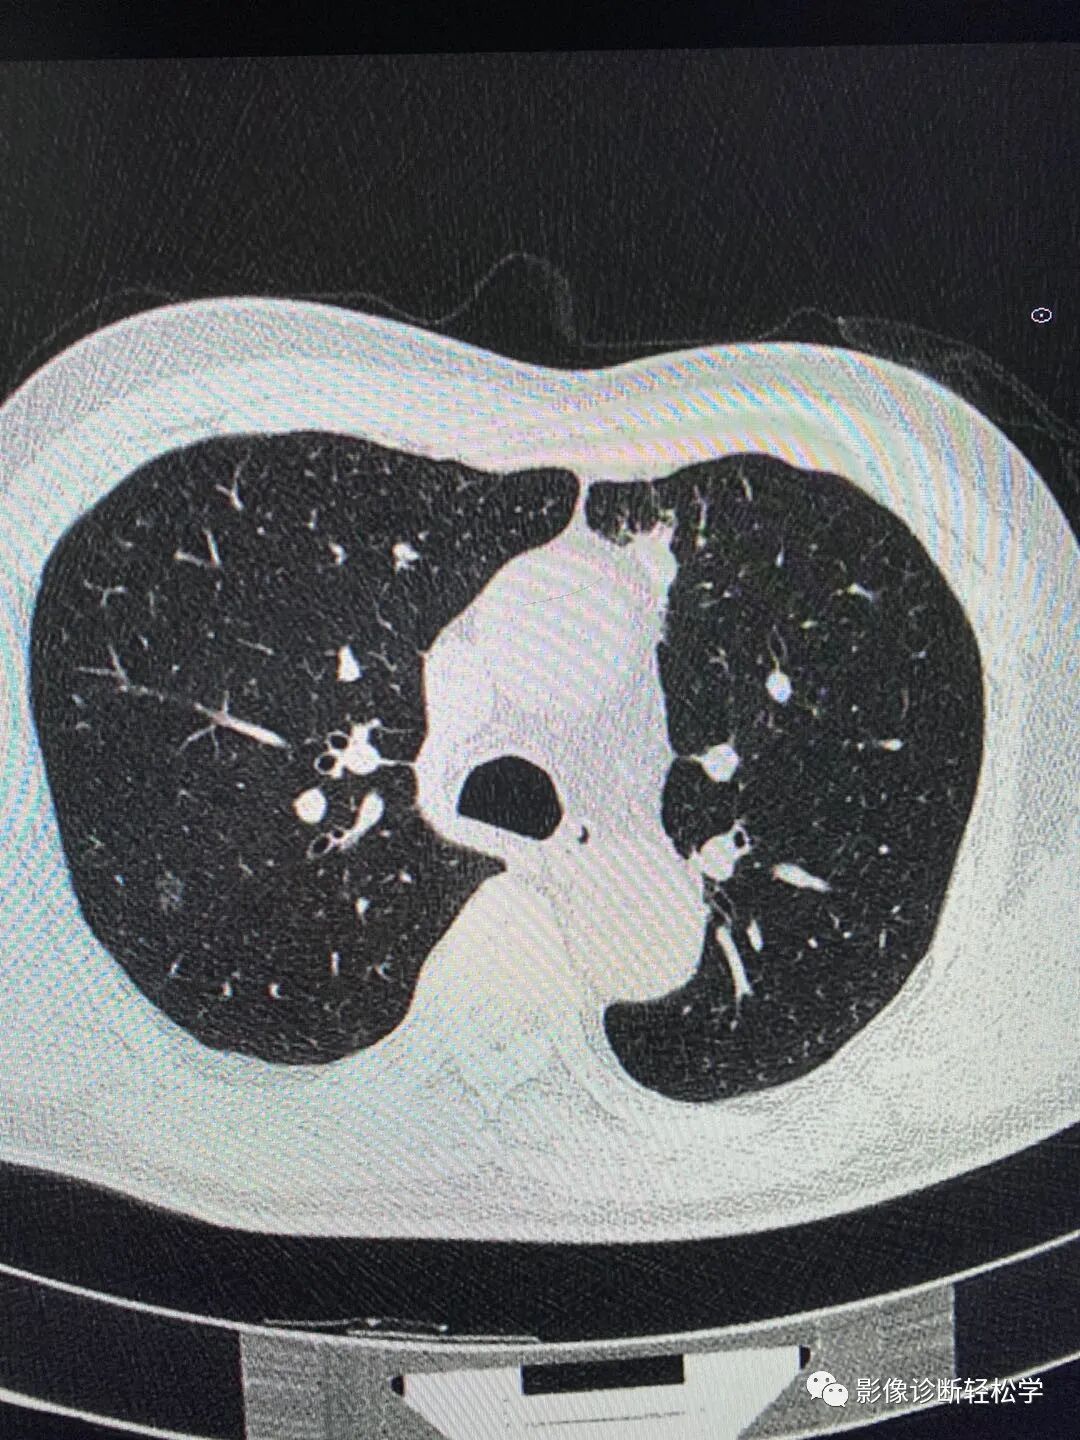

多发磨玻璃结节

多发磨玻璃结节怎么办北京患者6个磨玻璃结节3个微浸润腺癌